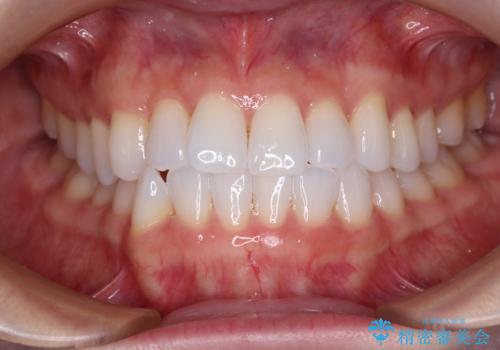

前歯のデコボコをインビザラインで綺麗に

- 上下前歯の叢生を気にして来院された患者様です。

インビザラインでの治療を希望されていて、デコボコの程度が中等度であり、安価なパッケージにて対応可能と判断されたため、インビザライン・モデレートを用いて矯正治療を行うこととしました。